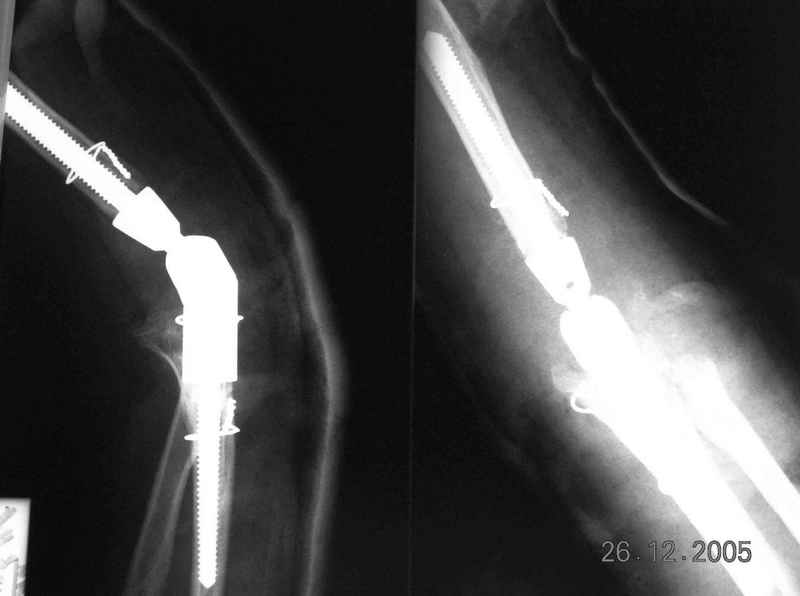

Re: Болтающийся ложный сустав дистального плеча

Уважаемый Ильдар, в ноябре 2005 г. мы оперировали практически полностью идентичную ситуацию у больного с гемофилией, поставили модифицированный

эндопротез локтевого сустава типа Сиваша с хорошим результатом. На заводе-производителе (в нашем случае - завод ЦИТО, но есть еще ООО

Эндосервис т/ф (095) 221-06-18, 500-41-30, 513-54-32 ) можно заказать протез этого типа по индивидуальным размерам для восполнения дефицита длины плечевой кости. Сейчас есть и более дорогие коммерческие эндопротезы фирмы Stryker. Наиболее активно оперируют локоть в ЦИТО, у нас тоже есть

собственный небольшой опыт эндопротезирования локтевого сустава.